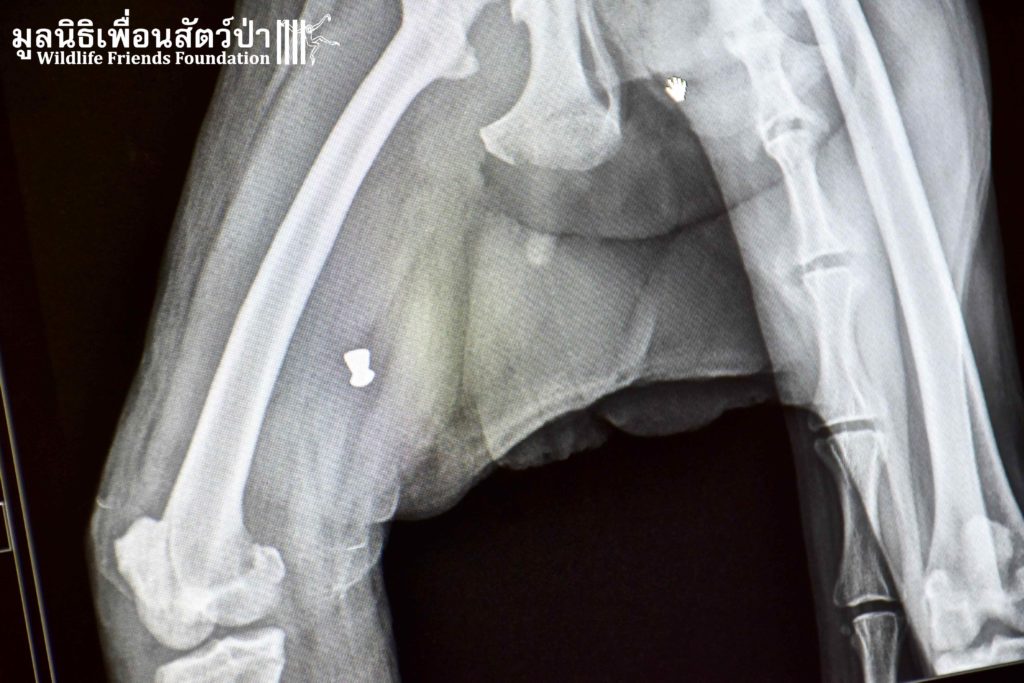

It was raining long-tailed macaques (Macaca fascicularis) in the hospital this week! Our first patient, Auan, arrived 2 months ago after being hit by a car. Although no breaks or dislocations were found, his radiographs revealed four old bullets lodged in his spine, thigh, ankle, and arm. His right leg suffered additional extensive abrasions from the car accident. Our hospital staff surmise that he has nerve damage that led to him painlessly dragging around his disabled limb, thus getting it infected. We decided to amputate this leg to avoid further complications. Because he is a large adult male, we are hopeful that he can be successfully released after he recovers and passes observation in quarantine.

Our second amputation of the day was of another long-tailed macaque, Bucky, who first came to us several months ago after falling out of a tree. He belongs to an urban macaque troop that is fed by a local community in Bangkok. They trapped and brought him to WFFT after noticing he had stopped using his arm. Once again, no breaks or dislocations were found in his radiographs but a fresh bullet wound was discovered in his disabled arm. It was removed and he was returned to his troop. However, he was brought back to WFFT this week because he still wasn’t using his arm. To avoid future risks of injury and sepsis, this arm was amputated after Auan’s leg amputation. After his recovery he will be returned to his troop in Bang Khun Thian, Bangkok.